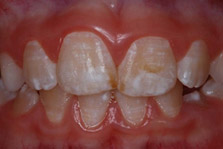

Dental fluorosis (DF) results from the ingestion of excessive amounts of fluoride, from all sources, during tooth development. This results in dysmineralization of the enamel. Very mild/mild DF presents as barely discernable white striae, and mottled areas of enamel.1Denbesten P, Li W. Chronic fluoride toxicity: dental fluorosis. Monogr Oral Sci 2011;22:81-96.,2Fejerskov O, Kidd E. Dental Caries - The disease and its clinical management. 2nd ed. USA: Wiley-Blackwell, 2008 These can be a cosmetic problem. (Figure 1) In contrast, severe DF results in pitted and malformed areas of enamel with porosities, brittle enamel, and altered dental morphology.1Denbesten P, Li W. Chronic fluoride toxicity: dental fluorosis. Monogr Oral Sci 2011;22:81-96.,2Fejerskov O, Kidd E. Dental Caries - The disease and its clinical management. 2nd ed. USA: Wiley-Blackwell, 2008